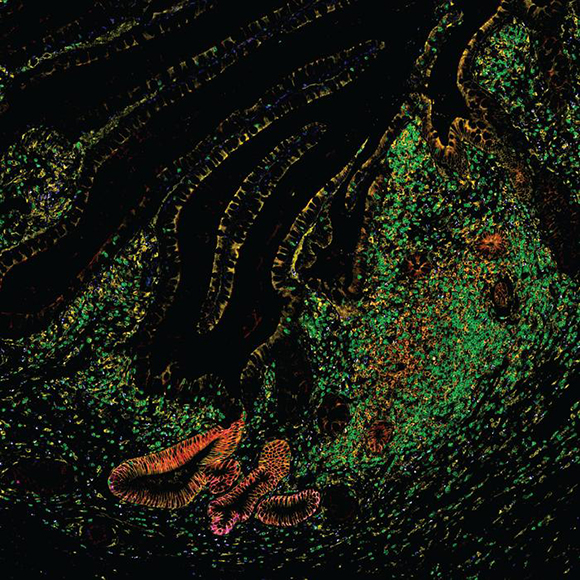

הקפיצה הטכנולוגית הבאה הובילה לטכנולוגיה שמאפשרת לקבוע את הרצף הגנטי (ה-DNA) של תא בודד, ולאחר מכן גם לרצף את ה-RNA שלו. תאי מעי מתוך אטלס התאים | Grace Burgin, Noga Rogel & Moshe Biton, Klarman Cell Observatory, Broad Institute

בין התאים של אנשים בריאים לעומת מידע על 1.6 מיליון תאים של חולי מחלות מעיים דוגמת קרוהן, צליאק, כיבים וסרטן. תאי מעי של חולה במחלת מעי דלקתית | מתוך המאמר A. Oliver, N. Huang, R. Li, et al. 2024

האטלסים של הרקמות השונות צפויים לשמש בסיס להשוואה עבור מחקרים עתידיים. תאי מעי של חולה במחלת מעי דלקתית | מתוך המאמר A. Oliver, N. Huang, R. Li, et al. 2024